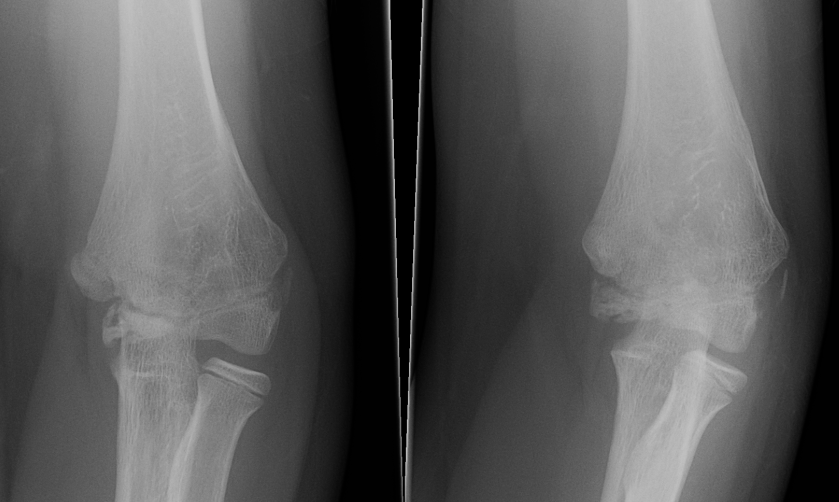

- xray other arm

Injured left elbow v injury right elbow

Internal oblique xray

Edmonds et al J Paediatr Orthop 2021

- 140 cases lateral condyle fracture treated non operatively

- displacement < 1.2 mm on internal oblique had failure rate of 58%

- displacement > 1.2 mm on internal oblique had failure rate of 1%

Kurtulmus et al Eur J Orthop Surg Traumatol 2014

- 27 patients with < 2 mm displacement on AP view

- 16 found to have > 2 mm displacement on subsequent internal oblique view